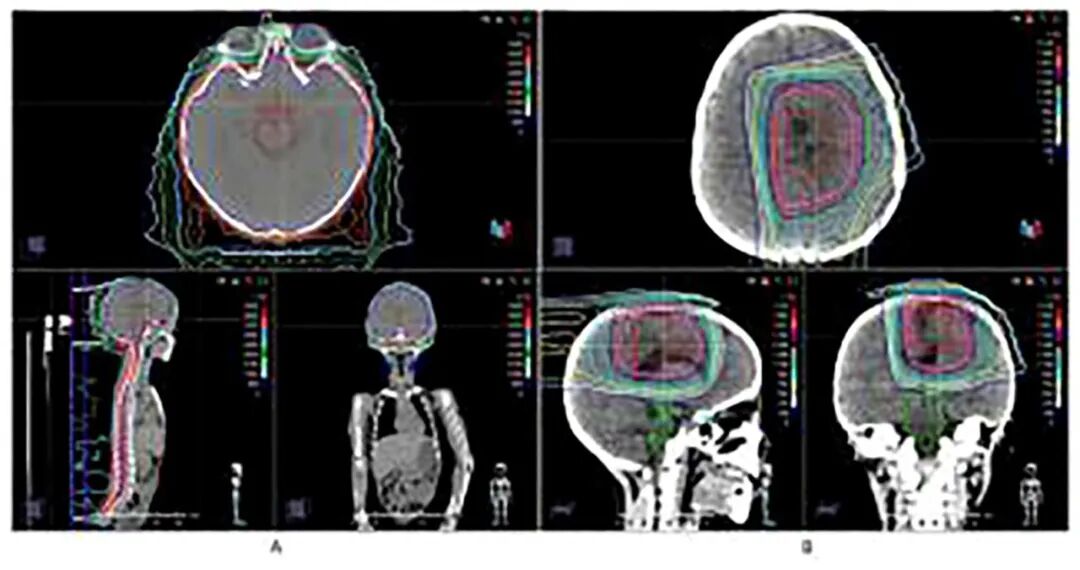

在为患儿进行了大范围的安全手术切除后,治疗团队选择了医院的质子治疗(PBT)进行术后辅助放疗。质子治疗凭借其独特的“布拉格峰”物理优势,能够将放射剂量精准集中在肿瘤区域,同时最大限度地保护周围的正常脑组织。这一步不仅是精准的初步治疗,更是一次极具远见的“布局”——通过减少对健康组织的损伤,为后续可能需要的再次放疗保留了宝贵的“窗口期”。

第二步:“伽马刀”精准“收官”,完成最后一击

质子治疗后,团队曾采用靶向药物治疗以稳定病情。由于仍有少量肿瘤残留,在进行二次手术后,团队果断启用伽马刀(GKRS)进行“最后一击”。正是得益于前期质子治疗对周围正常组织的良好保护,才使得后续高剂量的、高度聚焦的伽马刀治疗得以安全、有效实施,最终对残余病灶进行了彻底处理。